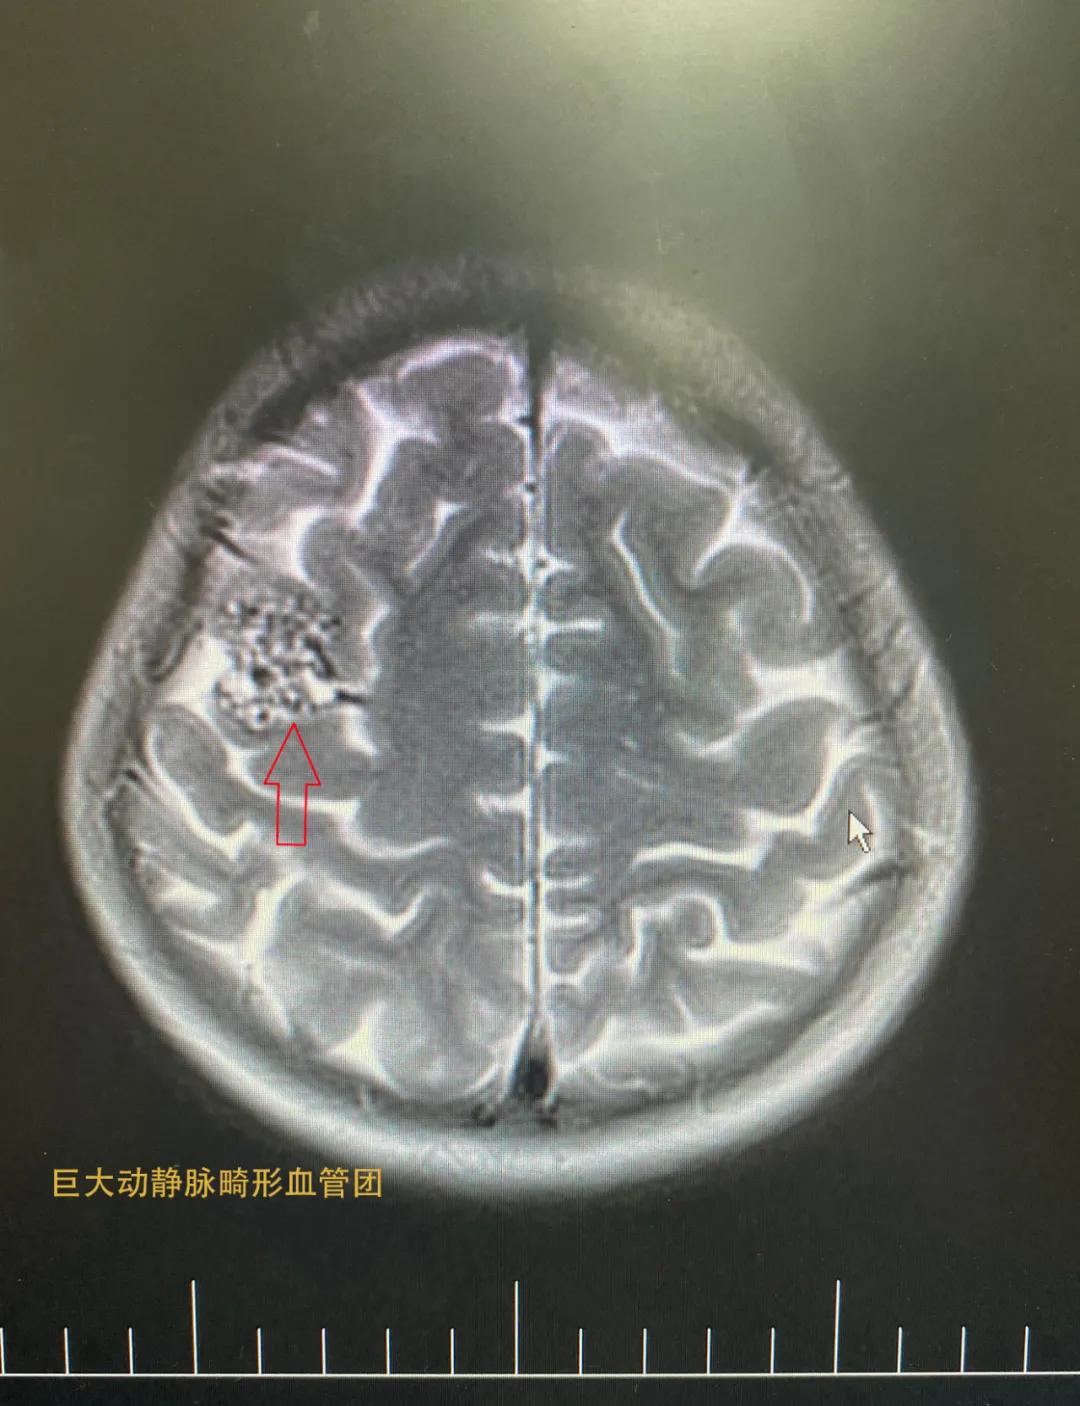

检查结果显示,患者右侧顶部动静脉畸形(供血为大脑中动脉远段分支血管,引流静脉为上矢状窦皮层浅静脉),进一步进行脑血管造影检查——患者右顶叶中央前回功能区动静脉畸形血管团。

术前检查片子